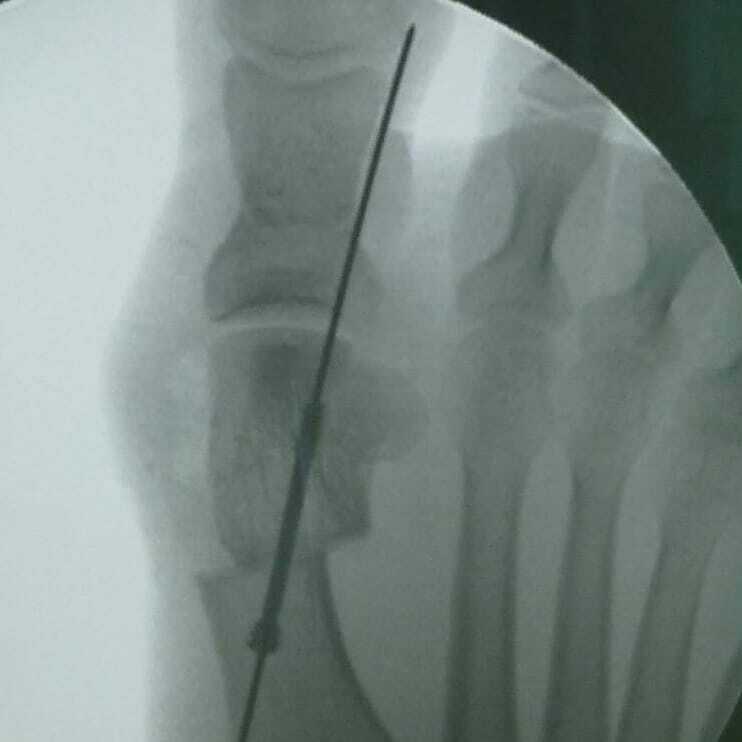

Фиксация винтами при операциях на стопах — хорошо или плохо?